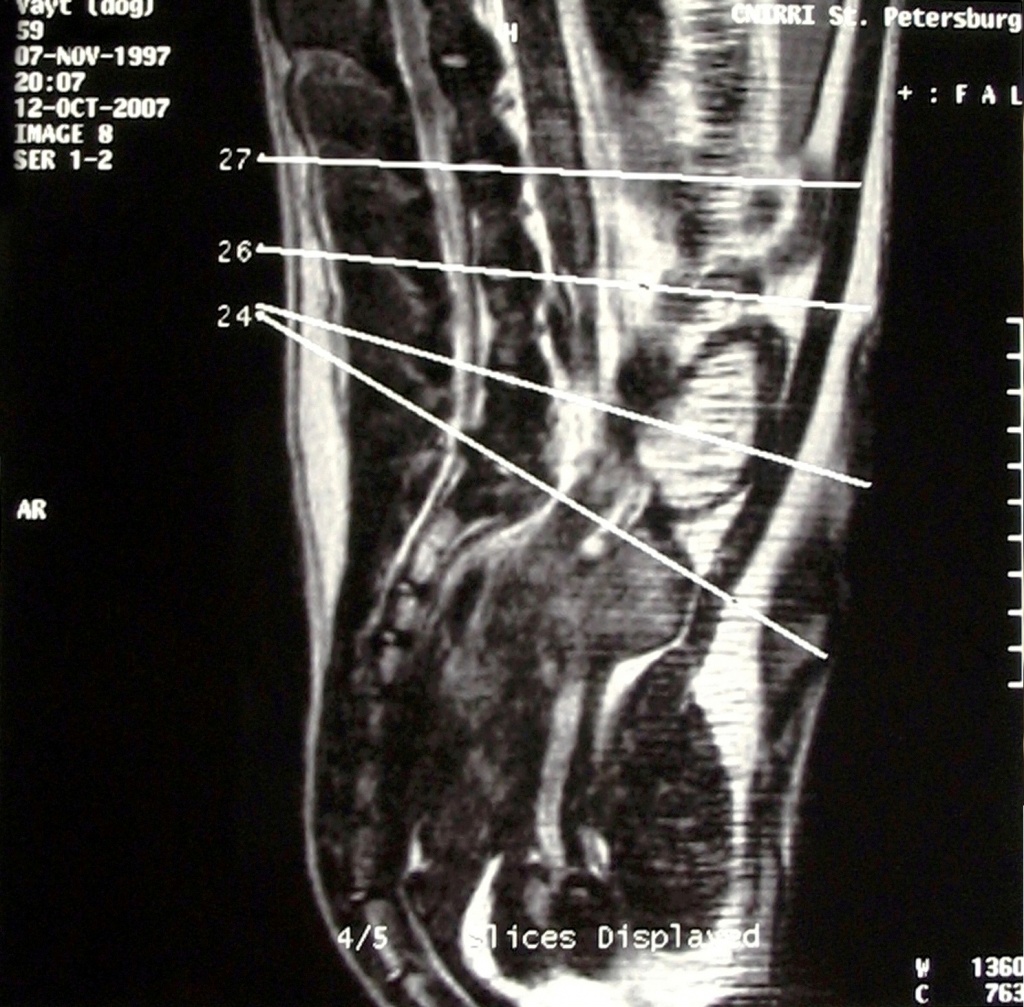

- ΠΠ°Π³Π½ΠΈΡΠ½ΠΎ-ΡΠ΅Π·ΠΎΠ½Π°Π½ΡΠ½Π°Ρ ΡΠΎΠΌΠΎΠ³ΡΠ°ΡΠΈΡ (ΠΠ Π’). ΠΠ±ΡΠ»Π΅Π΄ΠΎΠ²Π°Π½ΠΈΠ΅ ΠΏΠΎΠ·Π²ΠΎΠ»ΡΠ΅Ρ ΠΏΠΎΠ»ΡΡΠΈΡΡ ΠΌΠ°ΠΊΡΠΈΠΌΠ°Π»ΡΠ½ΠΎ ΡΠΎΡΠ½ΡΠ΅ Π΄Π°Π½Π½ΡΠ΅. ΠΠ° ΡΡΠ΅Ρ ΠΌΠ΅ΡΠ½ΡΡ ΡΠ½ΠΈΠΌΠΊΠ°Ρ ΠΏΠΎΠ·Π²ΠΎΠ½ΠΎΡΠ½ΠΈΠΊΠ° Π²ΡΠ°Ρ ΡΠ²ΠΈΠ΄ΠΈΡ ΠΈΠ·ΠΎΠ±ΡΠ°ΠΆΠ΅Π½ΠΈΠ΅ Π²Π½ΡΡΡΠ΅Π½Π½ΠΈΡ ΠΎΡΠ³Π°Π½ΠΎΠ² Π²ΡΡΠΎΠΊΠΎΠΉ ΡΠΎΡΠ½ΠΎΡΡΠΈ. ΠΠ»Π΅ΠΊΡΡΠΎΠΌΠ°Π³Π½ΠΈΡΠ½ΡΠ΅ Π²ΠΎΠ»Π½Ρ ΠΎΠ±Π»ΡΡΠ°ΡΡ ΡΠ΅Π»ΠΎΠ²Π΅ΠΊΠ° ΠΈ ΠΏΡΠ΅ΠΎΠ±ΡΠ°Π·ΡΡΡΡΡ Π½Π° ΡΠΊΡΠ°Π½Π΅ ΠΊΠΎΠΌΠΏΡΡΡΠ΅ΡΠ°.

ΠΠ΅ΠΊΠΎΡΠΎΡΡΠΌ Π±ΠΎΠ»ΡΠ½ΡΠΌ Π΄Π»Ρ ΠΏΠΎΠ»ΡΡΠ΅Π½ΠΈΡ Π΄ΠΎΠΏΠΎΠ»Π½ΠΈΡΠ΅Π»ΡΠ½ΠΎΠΉ ΠΈΠ½ΡΠΎΡΠΌΠ°ΡΠΈΠΈ ΠΏΡΠΈ ΡΠΈΠ½Π΄ΡΠΎΠΌΠ΅ ΠΊΠΎΠ½ΡΠΊΠΎΠ³ΠΎ Ρ Π²ΠΎΡΡΠ° ΠΏΠΎΠ·Π²ΠΎΠ½ΠΎΡΠ½ΠΈΠΊΠ° Π΄ΠΎΠΊΡΠΎΡΠ° Π½Π°Π·Π½Π°ΡΠ°ΡΡ ΠΎΠ±ΡΠΈΠΉ Π°Π½Π°Π»ΠΈΠ· ΠΊΡΠΎΠ²ΠΈ. ΠΠ°ΠΈΠ±ΠΎΠ»Π΅Π΅ ΠΈΠ½ΡΠΎΡΠΌΠ°ΡΠΈΠ²Π½ΡΠΌΠΈ ΡΠ²Π»ΡΡΡΡΡ ΠΌΠΈΠ΅Π»ΠΎΠ³ΡΠ°ΡΠΈΡ ΠΈ ΠΠ Π’.

ΠΠ Π’ Π΄ΠΈΠ°Π³Π½ΠΎΡΡΠΈΠΊΠ° ΠΎΠ±Π»Π°Π΄Π°Π΅Ρ Π±ΠΎΠ»Π΅Π΅ Π΄ΠΈΠ°Π³Π½ΠΎΡΡΠΈΡΠ΅ΡΠΊΠΈΠΌ ΡΠΈΡΠΎΠΊΠΈΠΌ ΡΠΏΠ΅ΠΊΡΡΠΎΠΌ ΠΈ ΡΠΏΠΎΡΠΎΠ±Π½Π° Π²ΡΡΠ²ΠΈΡΡ Π΄Π°ΠΆΠ΅ ΠΌΠ΅Π»ΠΊΠΈΠ΅ Π½Π°ΡΡΡΠ΅Π½ΠΈΠ΅, ΠΏΡΠΈΠ·Π½Π°ΠΊΠΈ ΠΊΠ°Π»ΡΡΠΈΠ½ΠΈΡΠΎΠ²Π°Π½ΠΈΡ, Π²ΠΎΡΠΏΠ°Π»Π΅Π½ΠΈΡ. ΠΠ΅ΡΠ°Π»ΡΠ½ΠΎΠ΅ ΡΡΠ΅Ρ ΠΌΠ΅ΡΠ½ΠΎΠ΅ ΠΈΠ·ΠΎΠ±ΡΠ°ΠΆΠ΅Π½ΠΈΠ΅ Π½Π΅ ΡΠΎΠ»ΡΠΊΠΎ ΡΡΡΠ°Π½Π°Π²Π»ΠΈΠ²Π°Π΅Ρ Π΄ΠΈΠ°Π³Π½ΠΎΠ·, Π½ΠΎ ΠΈ ΠΏΠΎΠΌΠΎΠ³Π°Π΅Ρ ΠΎΠΏΡΠ΅Π΄Π΅Π»ΠΈΡΡ ΠΏΡΠΈΡΠΈΠ½Ρ ΠΏΠ°ΡΠΎΠ»ΠΎΠ³ΠΈΠΈ.

Π Π½Π΅ΠΊΠΎΡΠΎΡΡΡ ΡΠ»ΡΡΠ°Ρ ΡΡΠ΅Π±ΡΠ΅ΡΡΡ Π²ΡΠΏΠΎΠ»Π½Π΅Π½ΠΈΠ΅Β ΠΌΠΈΠ΅Π»ΠΎΠ³ΡΠ°ΡΠΈΠΈΒ β ΡΡΠΎ ΠΊΠΎΠ³Π΄Π° Π²Β ΡΠΏΠΈΠ½ΠΎΠΌΠΎΠ·Π³ΠΎΠ²ΠΎΠΉΒ ΠΊΠ°Π½Π°Π» Ρ ΠΏΠΎΠΌΠΎΡΡΡ ΠΏΡΠ½ΠΊΡΠΈΠΈ Π²Π²ΠΎΠ΄ΡΡΒ ΡΠ΅Π½ΡΠ³Π΅Π½ΠΊΠΎΠ½ΡΡΠ°ΡΡΠ½ΠΎΠ΅Β Π²Π΅ΡΠ΅ΡΡΠ²ΠΎ. ΠΠ΅ΡΠΎΠ΄ ΠΈΡΠΏΠΎΠ»ΡΠ·ΡΠ΅ΡΡΡ Π΄Π»Ρ Π΄Π΅ΡΠ°Π»ΡΠ½ΠΎΠ³ΠΎ ΠΈΠ·ΡΡΠ΅Π½ΠΈΡ ΡΡΡΡΠΊΡΡΡ ΠΊΠ°Π½Π°Π»Π° ΠΈ Π½Π΅ΡΠ²Π½ΡΡ ΠΎΠΊΠΎΠ½ΡΠ°Π½ΠΈΠΉ. ΠΠ΄Π½Π°ΠΊΠΎ ΠΈΡΡΠ»Π΅Π΄ΠΎΠ²Π°Π½ΠΈΠ΅ ΠΏΡΠΎΡΠΈΠ²ΠΎΠΏΠΎΠΊΠ°Π·Π°Π½ΠΎ Π΄Π»Ρ ΠΏΡΠΎΠ²Π΅Π΄Π΅Π½ΠΈΡ, Π΅ΡΠ»ΠΈ ΠΈΠΌΠ΅Π»ΠΈΡΡ Π½Π΅Π²ΡΠΎΠ»ΠΎΠ³ΠΈΡΠ΅ΡΠΊΠΈΠ΅ ΠΎΡΠ»ΠΎΠΆΠ½Π΅Π½ΠΈΡ ΡΠΏΠΈΠ½Π°Π»ΡΠ½ΠΎΠΉ Π°Π½Π΅ΡΡΠ΅Π·ΠΈΠΈ.

ΠΠ°Π³Π½ΠΈΡΠ½ΠΎ-ΡΠ΅Π·ΠΎΠ½Π°Π½ΡΠ½Π°Ρ ΡΠΎΠΌΠΎΠ³ΡΠ°ΡΠΈΡ (ΠΠ Π’) — ΡΡΠ°Π½Π΄Π°ΡΡΠ½ΡΠΉ ΠΌΠ΅ΡΠΎΠ΄ ΠΏΠΎΠ΄ΡΠ²Π΅ΡΠΆΠ΄Π΅Π½ΠΈΡ Π½Π°Π»ΠΈΡΠΈΡ ΡΠΈΠ½Π΄ΡΠΎΠΌΠ° ΠΊΠΎΠ½ΡΠΊΠΎΠ³ΠΎ Ρ Π²ΠΎΡΡΠ° ΠΈ ΠΏΠ»Π°Π½ΠΈΡΠΎΠ²Π°Π½ΠΈΡ Ρ ΠΈΡΡΡΠ³ΠΈΡΠ΅ΡΠΊΠΎΠ³ΠΎ Π»Π΅ΡΠ΅Π½ΠΈΡ.Π§Π΅ΠΌ ΡΠ°Π½ΡΡΠ΅ Π±ΡΠ΄Π΅Ρ Π΄ΠΈΠ°Π³Π½ΠΎΡΡΠΈΡΠΎΠ²Π°Π½ ΡΠΈΠ½Π΄ΡΠΎΠΌ ΠΊΠΎΠ½ΡΠΊΠΎΠ³ΠΎ Ρ Π²ΠΎΡΡΠ°, ΡΠ΅ΠΌ Π±ΠΎΠ»ΡΡΠ΅ Ρ ΠΏΠ°ΡΠΈΠ΅Π½ΡΠ° ΡΠ°Π½ΡΠΎΠ² Π½Π° ΠΏΠΎΠ»Π½ΠΎΠ΅ Π²ΡΠ·Π΄ΠΎΡΠΎΠ²Π»Π΅Π½ΠΈΠ΅ ΠΈ ΠΊΠ°ΠΊ ΠΌΠΎΠΆΠ½ΠΎ ΠΌΠ΅Π½ΡΡΠ΅ Π΄Π»ΠΈΡΠ΅Π»ΡΠ½ΡΡ ΡΠΈΠΌΠΏΡΠΎΠΌΠΎΠ² ΠΏΠΎΠ²ΡΠ΅ΠΆΠ΄Π΅Π½ΠΈΡ Π½Π΅ΡΠ²ΠΎΠ².